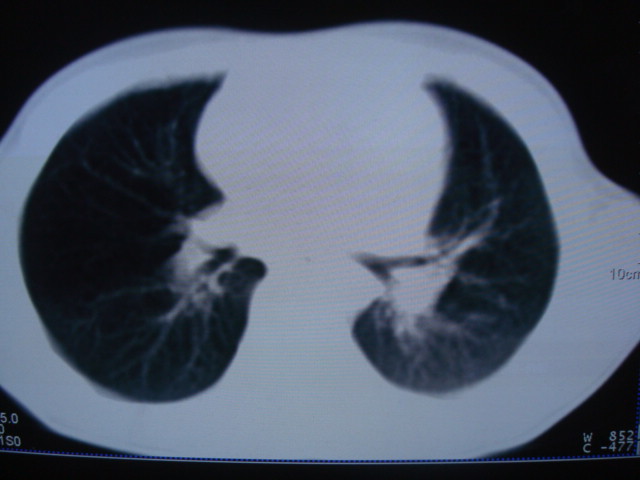

标题: PED0869:男,10岁,肺内多发结节+胸水

男,10岁,左胸痛,发热轻,血象高。后到省级权威医院治疗,病情明显好转,结果几天后公布。老机器,图像质量差,见谅。